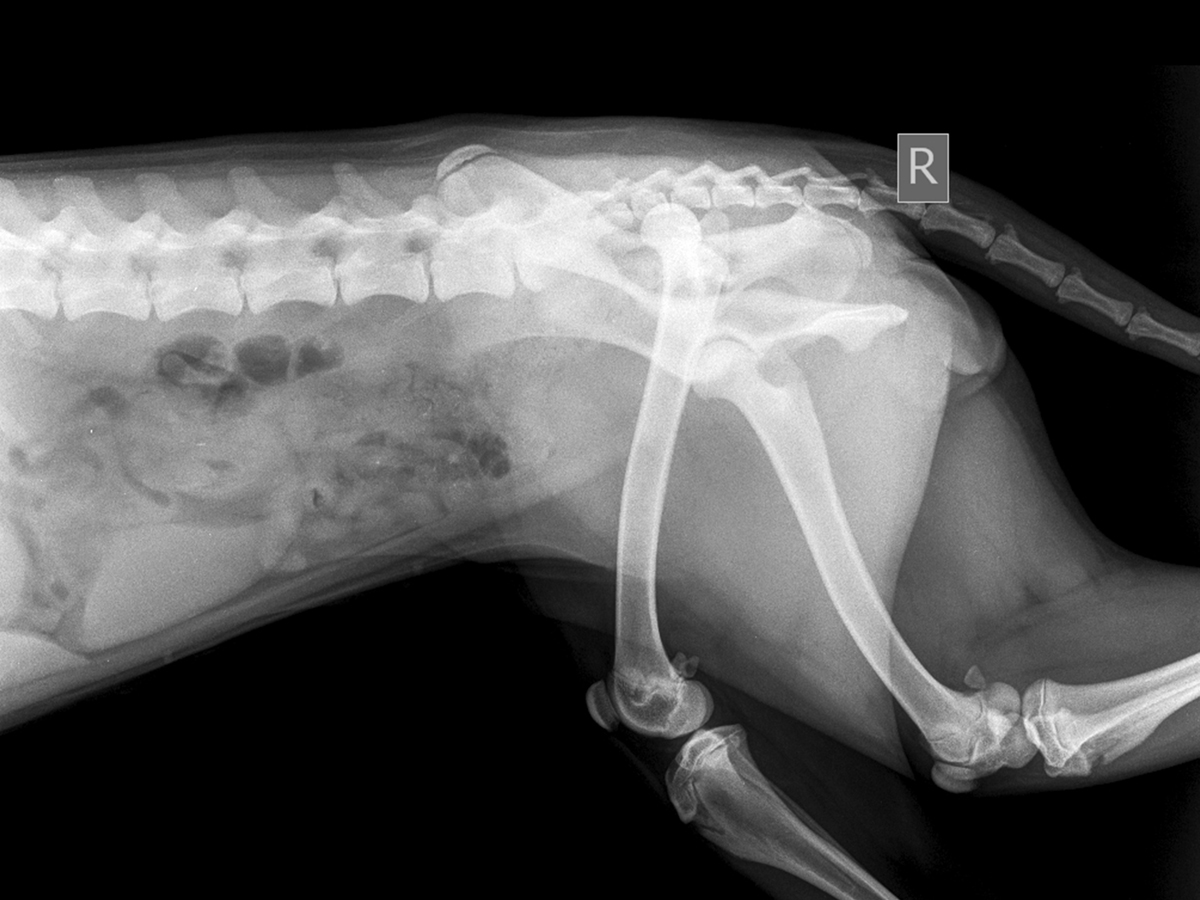

Hip dysplasia is a common skeletal condition where the protective cartilage around the hip joint erodes, leading to abnormal friction between the bones. This friction causes inflammation, resulting in pain, uneven walking, and poor support of body weight.

Common symptoms include an uneven gait or weakness in the rear legs. It is a common conditions for certain breeds, such as Golden Retrievers, Labradors, German Shepherds, Shiba Inus, and Poodle.

Total Hip Replacement is a surgery where the damaged parts of a pet’s hip joint are removed and replaced with artificial parts to help them move better and feel less pain. This is the only treatment that fully restores the range of motion and mobility while preventing hip dysplasia from recurring. This is a complex surgery that require to undergo special training.

- PennHIP (Hip Dysplasia Screening)